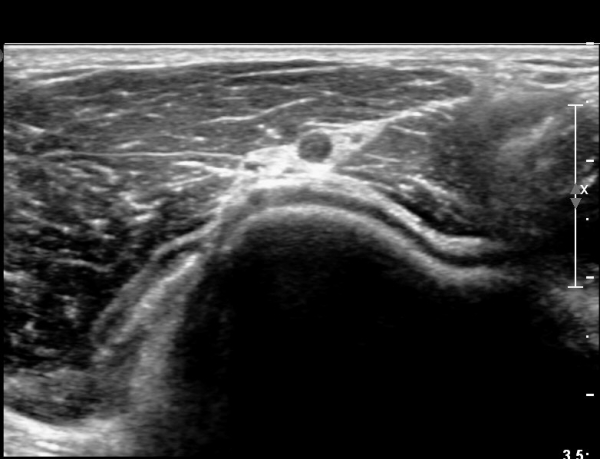

ÆÈ²ÞÄ¡ ¾Õ, Èİñ°£½Å°æ Ⱦ´Ü¸é °Ë»ç¿¡¼ Èİñ°£½Å°æÀÇ ºÎÁ¾ÀÌ °üÂûµÇ°í (»çÁø 1),